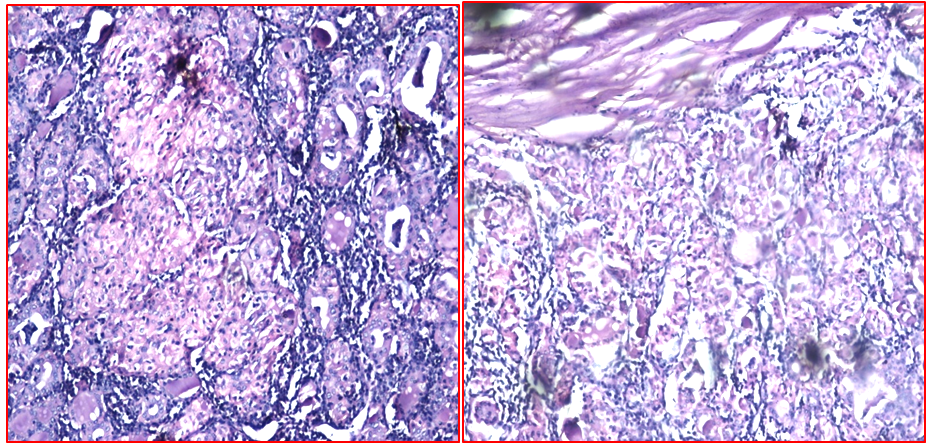

Figure 1 Hurthle cell adenoma on H&E HPE on x40, x10.

Figure 2 Hurthle cell adenoma on frozen and FNAC X40, X10.